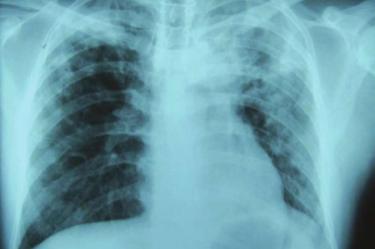

La enfermedad es causada por una bacteria que a menudo infecta los pulmones y es altamente transmisible cuando los enfermos tosen o estornudan. Aproximadamente una cuarta parte de la población mundial tiene una infección de tuberculosis latente, lo que significa que son portadores de la bacteria, pero no se han enfermado y no pueden transmitirla. Aquellos que albergan la bacteria tienen entre 5 y 10% de posibilidades de desarrollar tuberculosis.